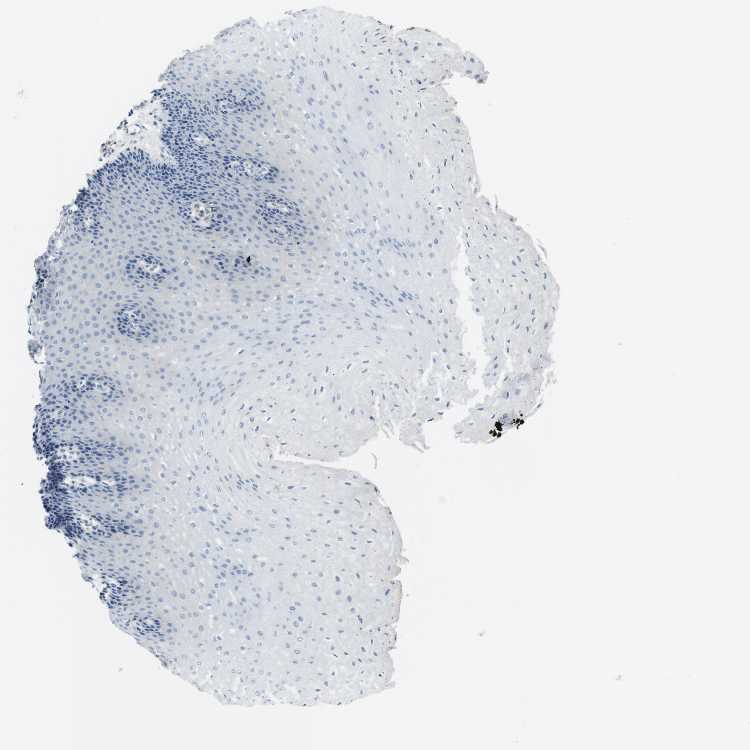

ESOPHAGUS - Antibody stainingi

Antibody staining in the annotated cell types in the current human tissue is reported as not detected, low, medium, or high, based on conventional immunohistochemistry profiling in selected tissues. This score is based on the combination of the staining intensity and fraction of stained cells.

Each image is clickable and will lead to virtual microscopy that enables deeper exploration of all samples and also displays staining intensity scores, fraction scores and subcellular localization as well as patient and tissue information for each sample.

Antibody CAB012703

Squamous epithelial cells Not detected

Female, age 70

Esophagus sample 130

nTPM: 0.9